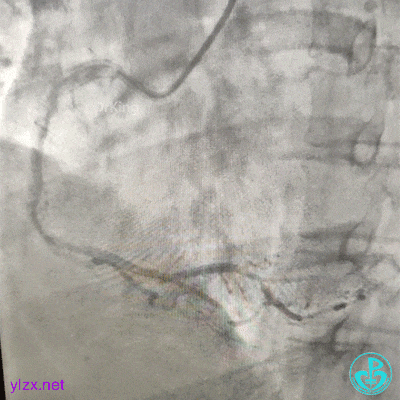

急诊造影

左冠脉造影发现左主干闭塞。